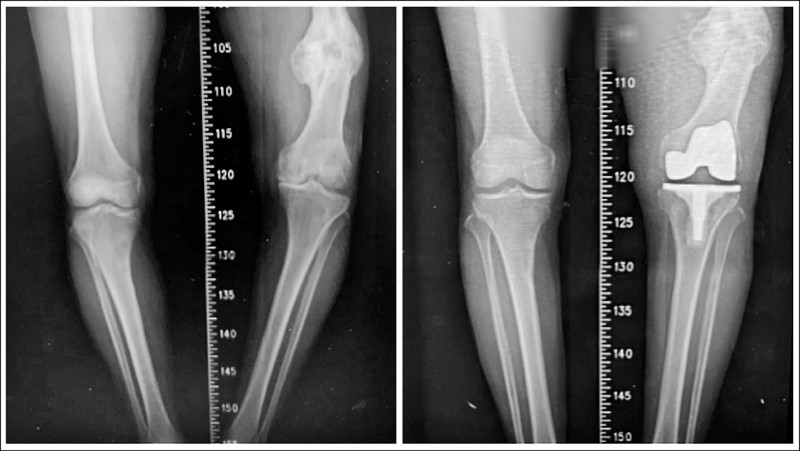

▲黃姓老翁的長短腿(左)在手術後(右)大幅改善。(豐原醫院提供)

87歲黃姓老翁年輕時,左側股骨骨折,因治療不佳致骨癒合不良,並出現內翻變形,造成下肢雙腳出現約2公分的長度差距,最後更擴大至近7公分,長年深受長短腳與膝蓋疼痛所苦,不僅步態不穩,更引發腰部與下肢不適,在接受人工膝關節置換手術後,成功改善症狀,重拾穩健步伐。

黃翁手術困難度在於要同時面對「陳舊性股骨骨折造成的骨骼變形」與「長達7公分的下肢長度差距」,因此,除了進行人工關節置換,還需進行精準的韌帶平衡,經輔以電腦導航與影像輔助技術,在修正骨骼角度的同時兼顧關節周圍韌帶平衡,避免造成膝關節不穩定,行動困難。

江福財表示,黃翁手術並未採用截骨矯正方式,而是單靠人工膝關節置換,直接解決患者最在意的長短腳問題,最終成功將雙腿長度差縮小至約2.5公分,大幅改善步態,術後患者無需輔具即可下床行走,逐步恢復生活自理能力,但術後仍須持續進行肌力訓練與步態矯正,以確保關節穩定性,並定期回診追蹤。